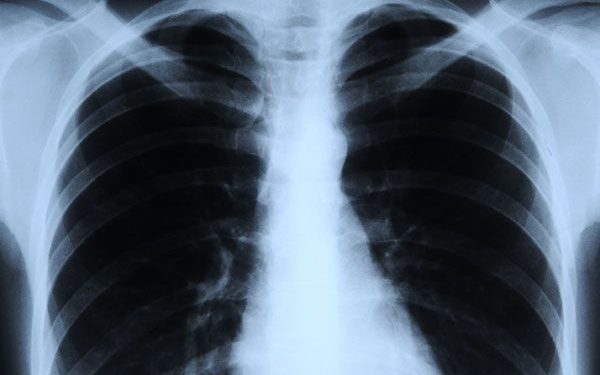

Medical imaging has numerous advantages for patients. Images of the human body are created using various methods, including ultrasound, magnetic resonance imaging, nuclear medicine, and X-rays. To enable physicians to see inside the body, identify and rule out medical problems, and diagnose diseases.

Much has recently been written about radiation, so it is important to understand radiation imaging, particularly the benefits to the patient and the associated risks. Let’s discuss the important uses of taking X-rays: